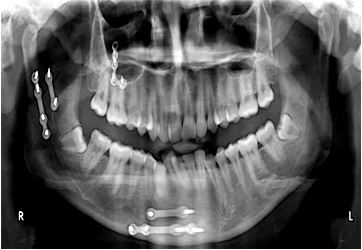

Background and Objectives: Mandibular fractures, often caused by trauma, can lead to significant functional and aesthetic impairments, including difficulty chewing and speaking, and facial deformities, especially when comminuted. This study compares bone density and thickness in patients with comminuted mandibular fractures resulting from gunshot wounds, using advanced radiological methods to determine treatment efficacy and inform clinical decisions.

Subjects and Methods: This retrospective study compared the treatment of comminuted mandibular fractures resulting from gunshot wounds at Sana'a Military Hospital. The study included patients who underwent open or closed reduction, and demographic data, injury characteristics, and post-treatment examinations were collected. Bone density and thickness were measured using cone-beam computed tomography (CBCT) or CT scans, and statistical analysis was performed to compare the two groups.

Results: The study included five patients in each group who underwent intermaxillary fixation (IMF) and open reduction internal fixation (ORIF). The age distribution of patients was heterogeneous, with 30% between 22 and 24 years old, 20% between 25 and 27 years old, 30% between 28 and 30 years old, and 20% over 30 years old. Malunion was the most common complication, followed by bone loss in 30% of patients. No significant differences in bone density and thickness were observed between the IMF and ORIF groups at the site of injury.

Conclusion: Ultimately, a patient's previous bone density is the determining factor in determining the appropriate treatment for a jaw fracture and is not a criterion for comparison between IMF and ORIF. Although both treatments have risks and benefits, the success of the outcome depends on the quality of the underlying bone to ensure stable healing.